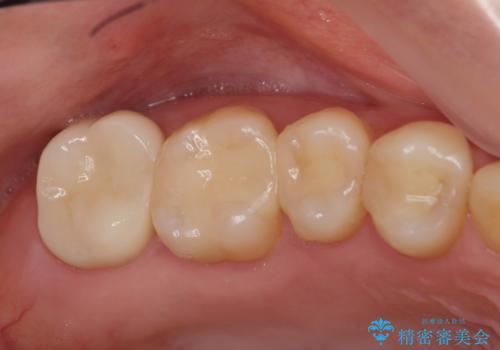

- 20.9万円(ジルコニアクラウン・仮歯・セラミックインレー)費用は治療当時の料金となります

天然歯と変わらない色調に優れるセラミック治療の仕上がりに満足いただくことができました。